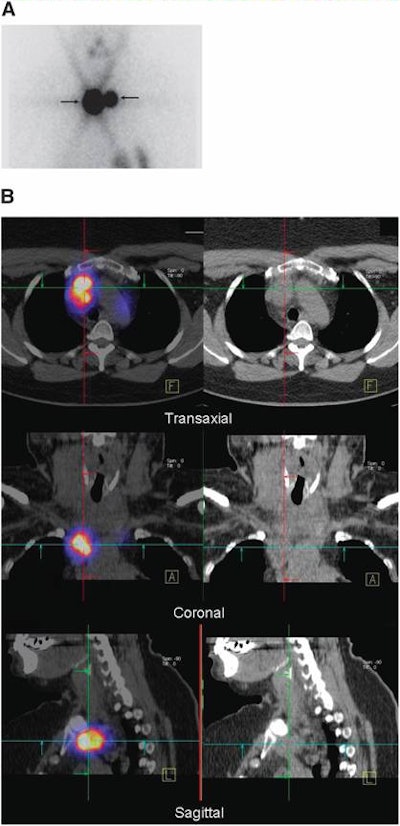

| Fifty-four-year-old woman with differentiated papillary thyroid carcinoma after total thyroidectomy and lymph node dissection of centrocervical and left lateral compartment. Image A is planar scintigraphy, which shows two iodine-131-avid foci interpreted as thyroid remnant. Image B is SPECT/CT (left column) and CT (right column), which demonstrate that these foci correspond to lymph node metastases in the superior mediastinum. Images courtesy of the Journal of Nuclear Medicine and University of Erlangen-Nürnberg. |